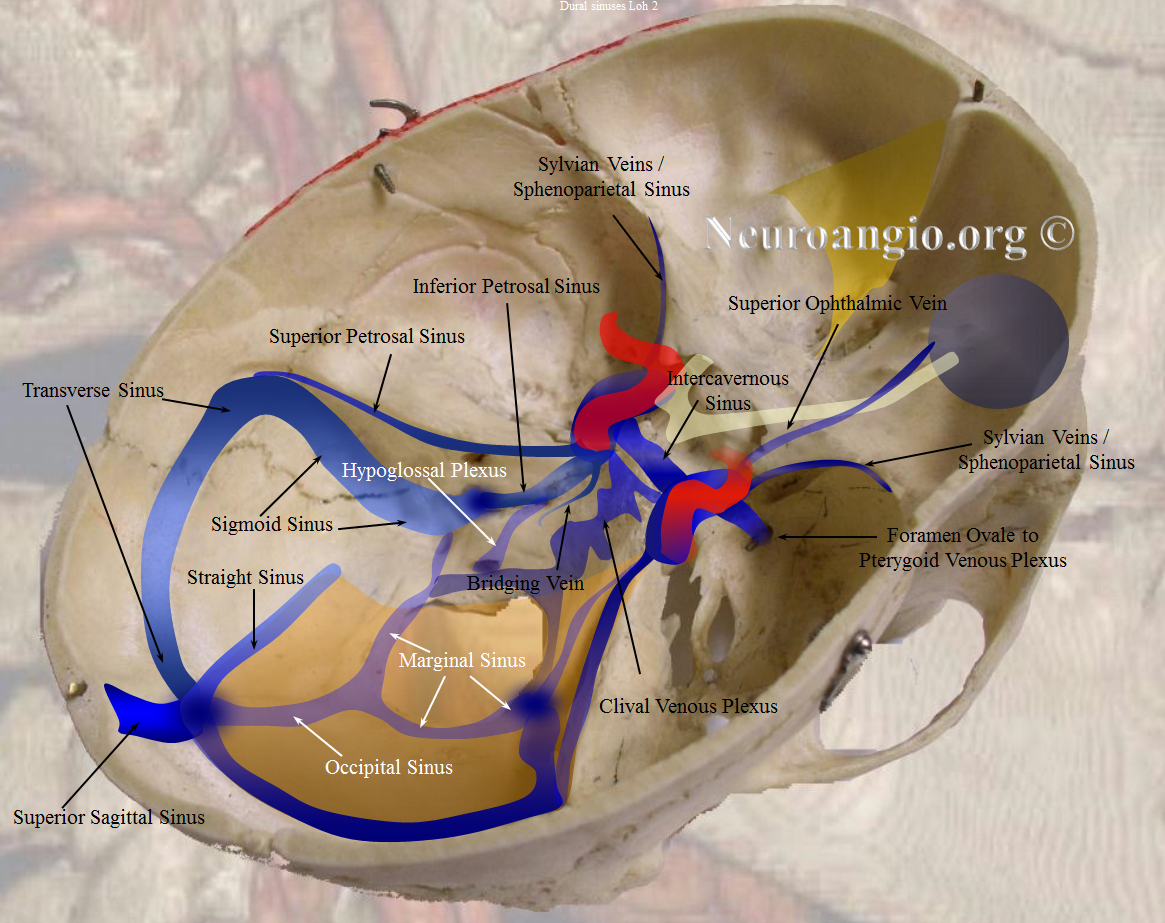

Cerebral Venous Sinuses

The most important feature regarding venous sinuses, and veins in general, is to keep in mind that veins are like rivers. The size of any vein or sinus is determined by the sum total of the tributaries it gathers, much like a river is exactly as large as the total volume of streams which feed it. Nearly all variations in venous size can be explained by this simple and powerful analogy.

The other point, no less important, is that the entire dura is a “tabula rasa’ for venous flow. Apart from the usual sinuses we will discuss, this page illustrates a tremendously rich spectrum of dural venous channels. The more one thinks of the dura not reading the book on where the classic sinuses should be, the easier comprehension of variants becomes and the better the complete venous picture is understood.

The main sinuses are well known. The superior sagittal sinus is nearly always present but can be variable in its anterior extent; its hypoplasia may be associated with dominance of the cavernous sinus draining the frontal lobes, prominence of normally small inferior sagittal sinus or large emissary veins — remember the rivers analogy. Often the SSS divides before reaching the torcula, an anatomical variant of no clinical significance but sometimes leading to unnecessary imaging to “conclusively” rule out an imaginary thrombus. The frequent variations at the torcular region bear witness to its late embryologic formation from the primordial venous plexus, substantially after the anterior and middle sinus have been formed.

The inferior sagittal sinus is smaller and inconstant. It usually collects tributaries from corpus callosum and cingulate gyrus regions, and drains into the straight sinus.

The transverse sinuses are often asymmetric, the left being more often hypoplastic than the right (pulsations of the right atrium are thought to be responsible for larger capacity of the right jugular system) The jugular foramen on smaller side is correspondingly small as well, helping distinguish developmental hypoplasia from acquired thrombosis.

The sigmoid sinuses are not always of the same caliber as the transverse ones, especially when a large vein of Labbe empties into the proximal sigmoid sinus to enlarge it substantially as compared with its transverse tributary. Extensive emissary veins (mastoid, occipital, condylar) often drain in part and occasionally in toto the transverse-sigmoid sinus complex, and the corresponding jugulars may be hypoplastic. Isolated findings of this nature are rarely due to consequences of pathologic shunting, and looking on bone windows for emissary channels can confirm this as a non-pathologic anatomical disposition.

The cavernous sinus collects extensive drainage and sports multiple egress routes. It has multiple compartments and may in fact be regarded, at least functionally, as a collection of separate entities. Not seeing it on an ICA injection does not mean its not there — only one compartment is hypoplastic. Embryologically, although the cavernous sinus is a very early structure, in its earliest form it does not seem to participate in the drainage of the brain — rather collecting tributaries of the future orbital/ophthalmic veins, facial and sphenopalatine systems. Even in the newborn, the connections between sylvian and basal venous systems and cavernous sinus are usually rudimentary– maturation of these connections is one mechanism which allows for stabilization of venous drainage in infants affected by high flow shunts such as some Vein of Galen Malformations, according to Lasjaunias. The developmentally late capture of the cavernous sinus by Sylvian and basal veins explains the marked variability in the extent of such capture in adults, while the ophthalmic vein to cavernous sinus connection is essentially constant.

The sphenoparietal sinus runs along the ridge of sphenoid lesser wing and collects tributaries of the Sylvian veins to empty into the cavernous sinus. Embryologically, a sinus by that name does exist, collecting the venous drainage of the very thin cortical mantle (future superficial sylvian veins), and directing it from the sphenoid area towards the sigmoid sinus, underneath the temporal lobe. This sinus usually disappears in the adult, except for some very rare instances. The very proximal portion of it appears to persist and connect to the cavernous sinus, however it is not clear whether this is in fact the case and if, instead, another channel does not run along the sphenoid ridge. Some believe this sinus in fact does not exist, and Sylvian veins drain directly into the cavernous sinus (See Cavernous Sinus page)

The superior petrosal sinus runs along the petrous ridge from cavernous to the sigmoid sinus. Inferior petrosal sinus runs down the petrous pyramid towards the jugular foramen or, more precisely, towards the very distal extra-cranial jugular vein.

An inconstant, in the adult, and more likely present than absent in the child, occipital sinus drains inferior from the torcula towards the marginal sinus which loosely surrounds the foramen magnum, to exit through it into suboccipital veins, perivertebral venous plexus, or around magnum to the jugular foramen.

Some sinuses are present less commonly than others: the more uncommon ones are labeled in white. The superior and inferior sagittal sinuses are not shown to full extent for clarity. Note how the sphenoparietal sinus runs along the edge of the lesser sphenoid wing, and superior petrosal sinus follows the petrous ridge. Most people have quite asymmetric sinuses.